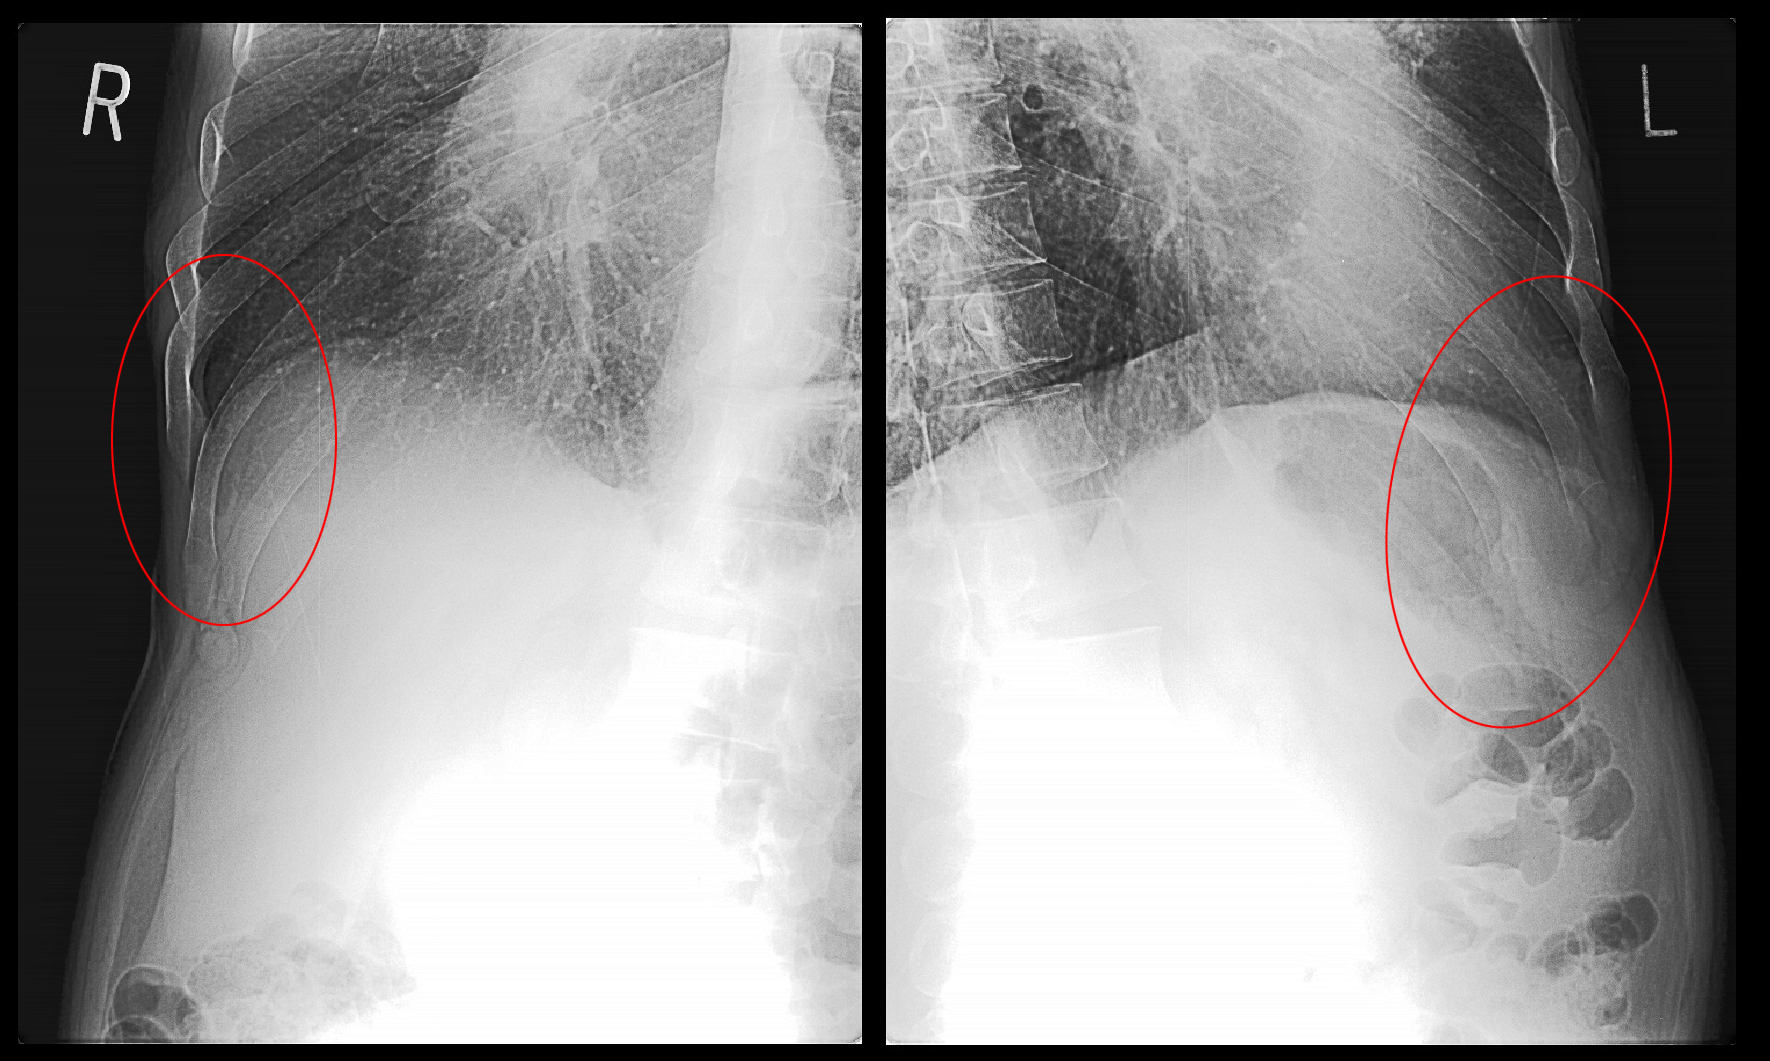

レントゲンで像では異常を認めません。